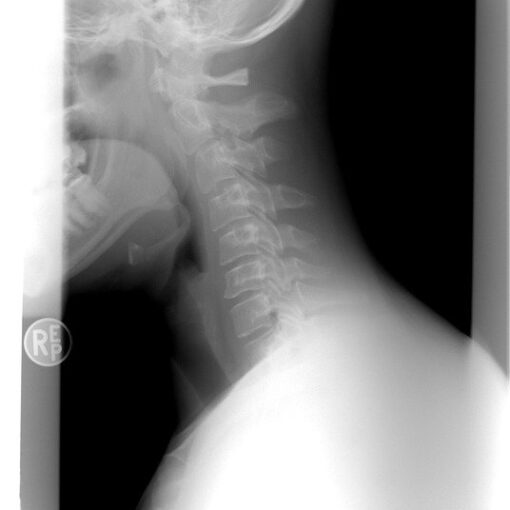

Die Atemwege

Erkältungsviren (Grippeviren) dringen über die Nasenschleimhaut in den Körper ein.

Bei einem gesunden Menschen sind die Nasenschleimhäute von Schleim überzogen, der sich ständig erneuert und Immunabwehrzellen in sich trägt. Hier werden potenzielle Erreger sofort abgetötet und über vermehrte Schleimbildung ausgeschieden. Entweder wir niesen, ‚schneutzen‘ oder ‚ziehen hoch‘. Bei letzterem wird der Schleim zumeist in den Rachen transportiert und reflexhaft hinuntergeschluckt, wo die Magensäure den letzten Überlebenden den Garaus macht.